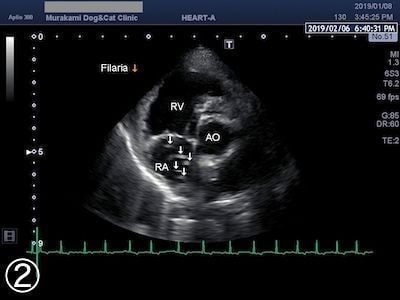

・胸部レントゲン検査

・心臓超音波検査

<検査結果見本>